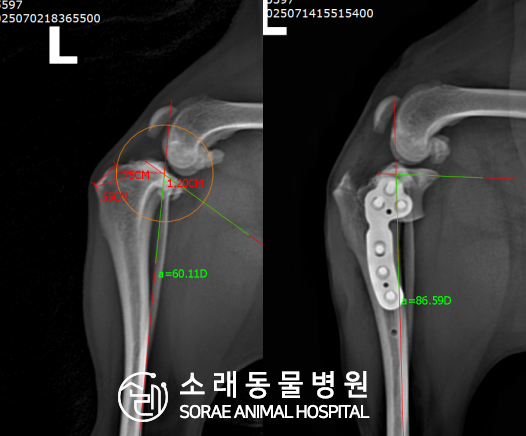

계산식으로 사전에 계획해두었던 플랜에 따라 경골을 절제하고

플레이트와 스크류를 사용하여 임플란트를 적용해 주었습니다.

반대 방향으로 밀려나 어긋나있던 대퇴골과 정강이가

제 자리를 찾으면서 무릎의 각도가 교정된 것을 확인할 수 있습니다